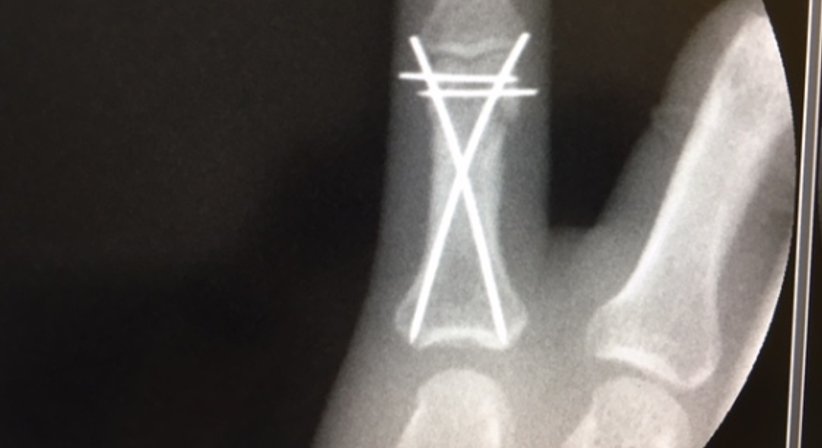

Versorgung von Knochenbrüchen

Osteosynthesen - OA Dr. Andreas Mondl - Unfallchirurg Wien 1220